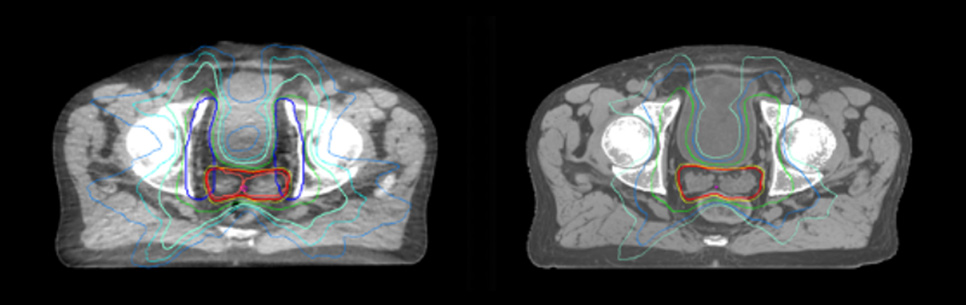

Prostate MR-only radiotherapy planning with use of rectal spacer

Hôpital de La Tour uses an implanted rectal spacer (SpaceOAR®, Boston Scientific) for patients receiving prostate radiotherapy to provide space between the rectum and prostate. 3D T2W TSE MRI provides excellent rectal spacer visualization and is used for OAR and target contouring. The dose plan is calculated on the MRCAT dataset.

Simulation imaging

Tranversal 3D T2W TSE with Compressed SENSE, acquired on Ingenia MR-RT 1.5T (left).

On-console generated MRCAT (right).

MR-based contouring and planning

MRCAT is primary image dataset for dose calculation (left).

3D T2W TSE MRI with 36 cm Field-of-View is used for delineation of prostate and organs at risk (right).